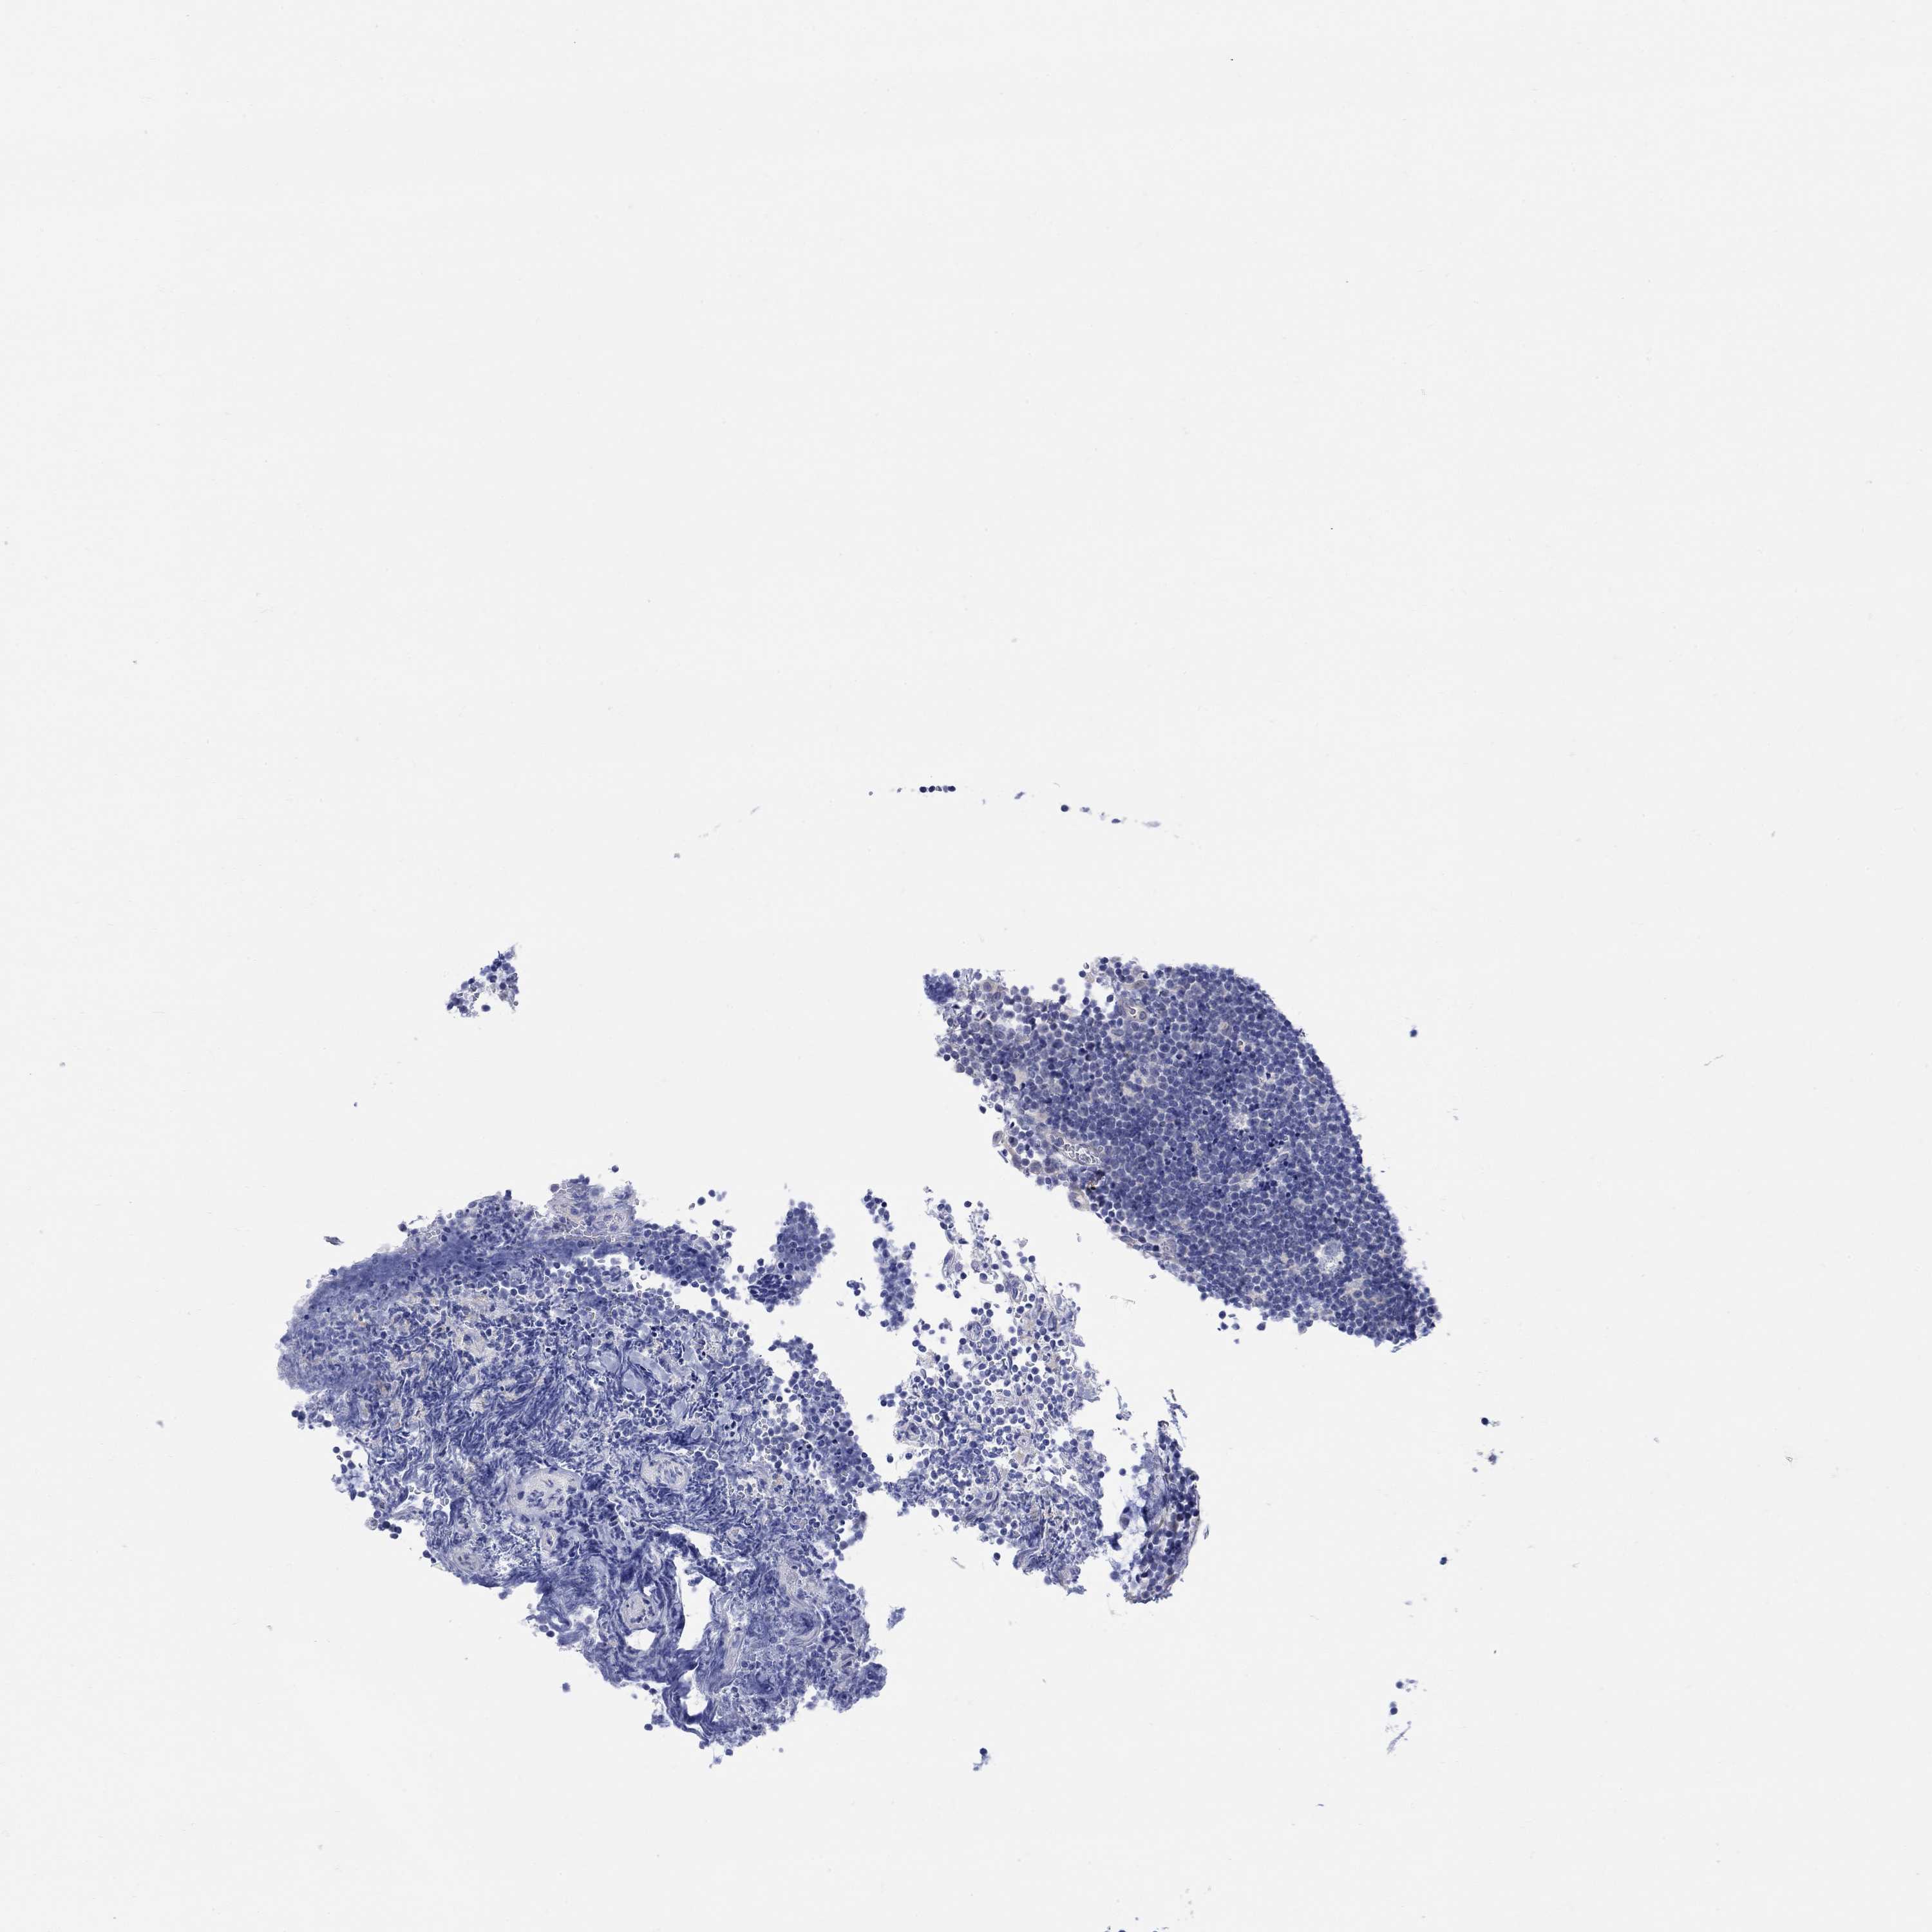

CANCER LYMPHOMA Show tissue menu

LYMPHOMA - Protein expressioni

A mouse-over function shows sample information and annotation data. Click on an image to view it in a full screen mode. Samples can be filtered based on level of antibody staining by selecting one or several of the following categories: high, medium, low and not detected. The assay and annotation is described here.

Each image is clickable and will lead to virtual microscopy that enables deeper exploration of all samples and also displays staining intensity scores, fraction scores and subcellular localization as well as patient and tissue information for each sample.

Antibody HPA068724

Staining

High

Medium

Low

Not detected

Intensity

Strong

Moderate

Weak

Negative

Quantity

>75%

75%-25%

<25%

None

Location

Nuclear

Cytoplasmic/membranous

Cytoplasmic/membranous,nuclear

Malignant lymphoma, non-Hodgkin's type, Low grade

Malignant lymphoma, non-Hodgkin's type, High grade

Hodgkin's disease, NOS